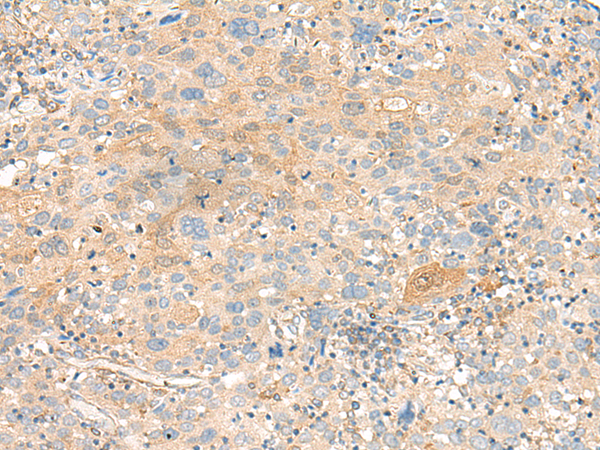

分类: 科研抗体货号: P13474别名: MEA-2; GCP170应用: WB,IHC反应种属: Human